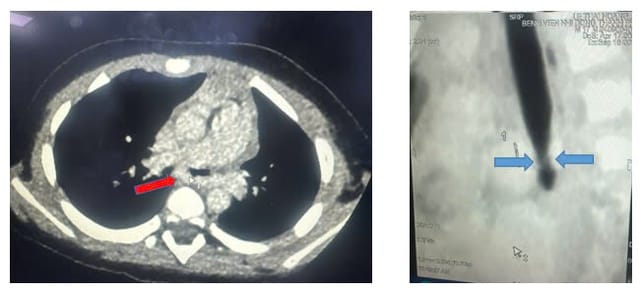

Tại Bệnh viện Nhi đồng Thành phố, trẻ tiếp tục được điều trị cơn hen phế quản nặng. Tình trạng trẻ có cải thiện nhưng vẫn khò khè nên được hội chẩn chụp CT scan ngực có cản quang.

Kết quả ghi nhận khí quản gốc chỗ chia đôi phế quản phải trái (carina) của bệnh nhi có động mạch phổi trái vòng qua phải ôm lấy rồi đi qua phổi trái gây chèn ép đường thở.

Các bác sĩ chuyên khoa Ngoại lồng ngực đã nhanh chóng tiến hành mổ đưa động mạch phổi trái về vị trí bình thường, khâu treo carina, phế quản gốc trái tránh mạch máu chèn.